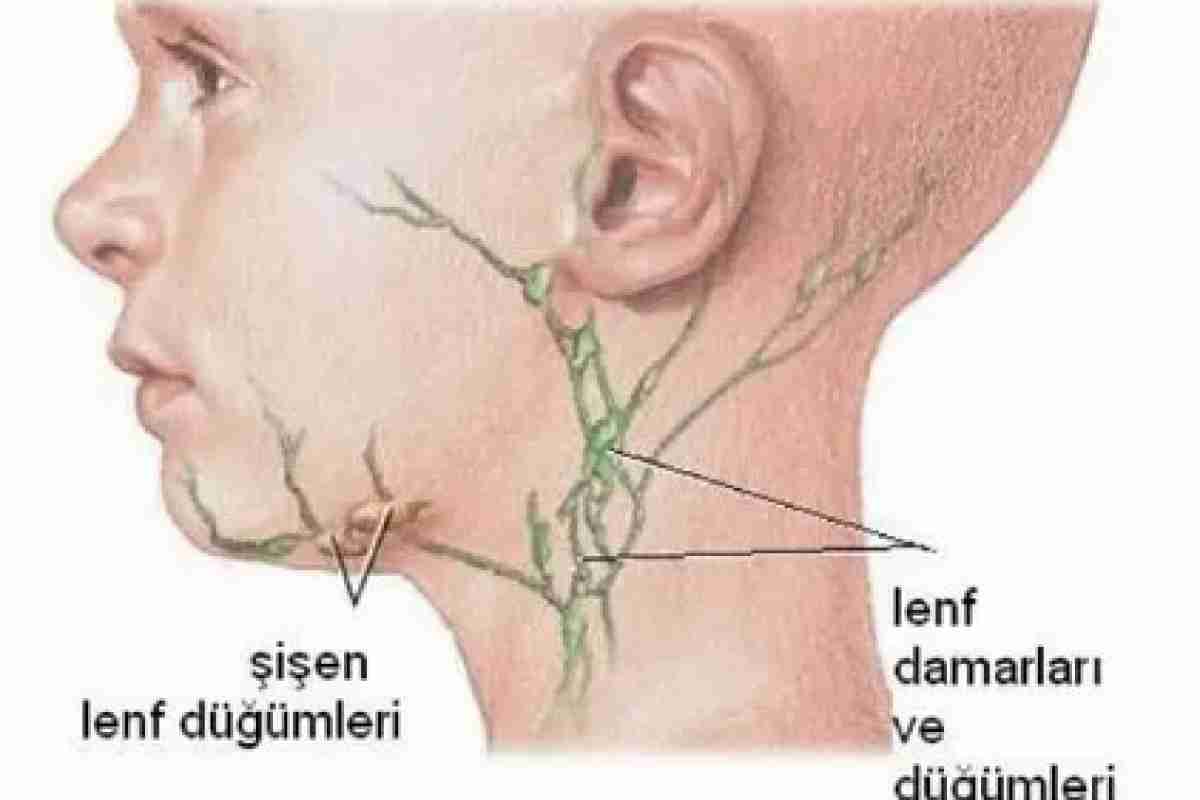

Изображения и схемы: как выглядит лимфа